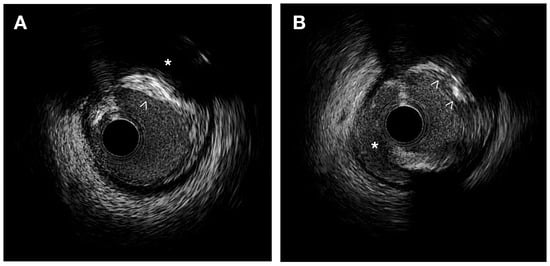

IVUS provides valuable information for the quantitative assessment of plaque thickness, cross-sectional area, plaque burden, and the remodeling index. It also allows for qualitative assessment, including the identification of the thin fibrous cap and the analysis of plaque composition. This analysis helps differentiate plaque components and assess plaque instability [9,12] (Figure 1).

Figure 1.

IVUS images. (A) Heterogeneous plaque with high echodensity areas (white arrowhead) and back shadowing (*) indicating calcification, as well as lower echodensity zones corresponding to a fibrous plaque. (B) Intimal disruption is associated with a dissection (*) and an irregular calcified plaque (white arrowheads).